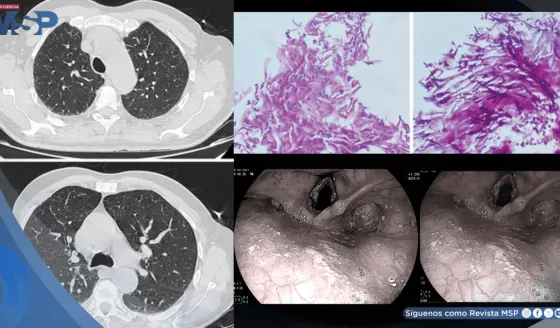

Candidiasis esofágica en hombre con asma tras automedicarse con fluticasona y tragar enjuague bucal

Prevención y detección temprana: Herramientas clave contra el cáncer de pulmón